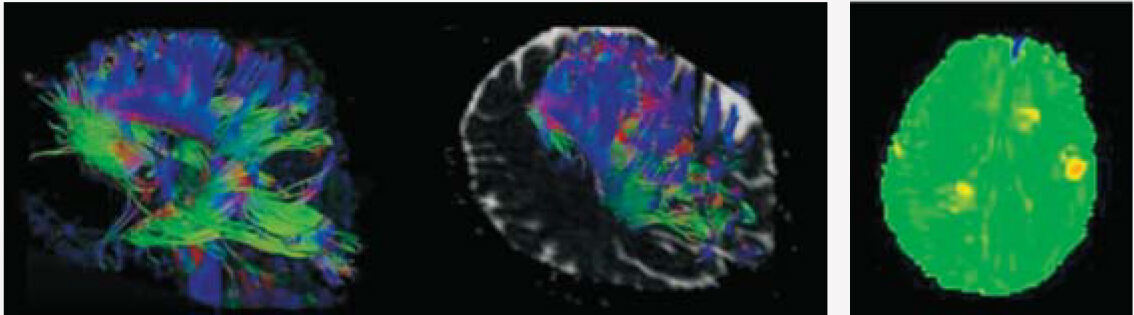

SuperMark 1.5T is a latest generation superconducting MRl system based on over 30 years of experience in research and development, which focuses on user's concerns. This system is equipped with a new upgraded hardware and software platforms with A-combi and Al technologies that benefit users a lot and deliver patients with more comfortable experiences. It features new user-friendly design, faster imaging speed, higher image quality and greatly improved work efficiency.

SuperMark 1.5T provides not only conventional pulse sequences and basic clinical applications, but also advanced functional applications. Moreover, it adopts brand new professional APEX operation system which ensures easy operation and fast diagnosis